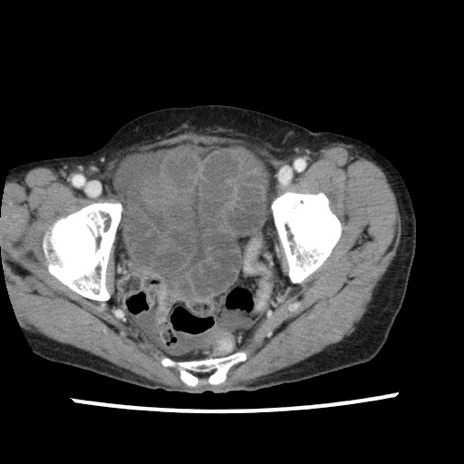

症例1(横断像)

症例

【症例】80歳代女性

【主訴】腹痛

【現病歴】8時間前から腹痛あり来院。

【既往歴】糖尿病、脂質異常症、子宮体癌にて子宮全摘術

【身体所見】意識清明・会話良好だが腹痛で苦悶様、全腹部にわたって反跳痛と圧痛あり

【データ】WBC 13600、CRP 0.14、LDH 224、CK 90